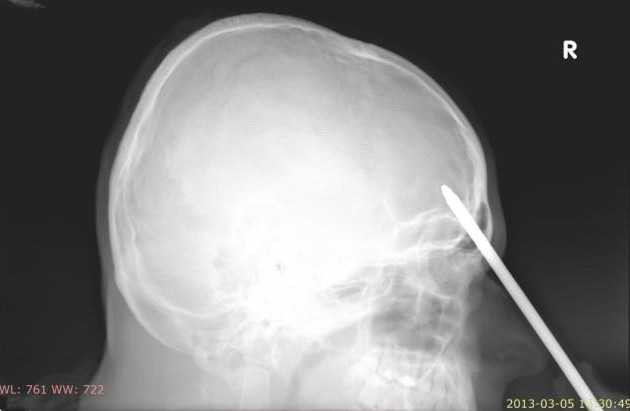

| Hình chụp cây tua vít đâm sâu đến 5cm vào trán nạn nhân. |

Theo các bác sĩ tại bệnh viện nơi nạn nhân được điều trị: "Chúng tôi đã phải mất hơn 3 giờ đồng hồ để phẫu thuật loại bỏ chiếc tua vít ra khỏi đầu nạn nhân. Cây tua vít đã đâm vào bên trong hộp sọ nạn nhân khoảng 5cm".

Sau đó khi tỉnh dậy thì anh ta cảm thấy đau nhức ở tay. Chỉ đến khi anh đứng dậy và nhìn vào gương xe thì mới thấy một cây tua vít đã đâm vào trán, xuyên qua hộp sọ của mình, vết thương cách trên mắt phải của anh một xíu".

May mắn là cây tua vít đã không gây ảnh hưởng nặng đến vùng mắt và bộ não của bệnh nhân.